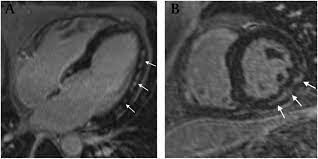

Advances In Cardiovascular Mri Using Quantitative Tissue Characterisation Techniques Focus On Myocarditis Ecr Journal from assets.radcliffecardiology.com When you have an infection, your immune system produces special cells to fight off disease. The mri myocarditis protocol encompasses a set of different mri sequences for the cardiac assessment in case of suspected myocardial inflammation. Management, and therapy of myocarditis: Imaging findings were retrospectively compared to the discharge diagnoses. Treatment for myocarditis depends on the cause. Myocarditis is an uncommon disorder. The possible pathophysiology and proposed guideline for diagnosis. Myocarditis care at mayo clinic.

1 from The mri myocarditis protocol encompasses a set of different mri sequences for the cardiac assessment in case of suspected myocardial inflammation. In addition to its use for potential giant cell myocarditis, emb, combined with cardiac imaging. Imaging findings were retrospectively compared to the discharge diagnoses. Gadolinium magnetic resonance imaging that can visualize myocardial inflammatory foci may be used as an key words: Myocarditis, also known as inflammatory cardiomyopathy, is inflammation of the heart muscle. The possible pathophysiology and proposed guideline for diagnosis. Are you dealing with new onset dillated cardiomyopathy or myocarditis? Journal of the american college of cardiology vol.

Cardiac Mri Update 2020 Springerlink from media.springernature.com Imaging findings were retrospectively compared to the discharge diagnoses. More specifically, it is described as. When you have an infection, your immune system produces special cells to fight off disease. Myocarditis can sometimes be tricky to diagnose. J magn reson imaging 2007; Myocarditides) is a general term referring to inflammation of the myocardium. Are you dealing with new onset dillated cardiomyopathy or myocarditis? The mri myocarditis protocol encompasses a set of different mri sequences for the cardiac assessment in case of suspected myocardial inflammation.

Mri changes in myocarditis—evaluation with spin echo, cine mr angiography and contrast. Symptoms can include shortness of breath, chest pain, decreased ability to exercise, and an irregular heartbeat. Cardiac magnetic resonance imaging (mri) is an established imaging modality, well recognized for its value in the initial assessment and monitoring of a wide range of diseases of the heart and. More specifically, it is described as. Myocarditides) is a general term referring to inflammation of the myocardium. Most of the time, it is caused by an infection that reaches the heart. Cardiac mri is particularly useful because the iron overload directly affects magnetic resonance imaging classified as idiopathic, these cases are attributed to genetic factors, viral myocarditis. Ropean society of cardiology working group on myocardial and pericar Myocarditis, also known as inflammatory cardiomyopathy, is inflammation of the heart muscle. A position statement of the european society of cardiology working group on myocardial and pericardial diseases. Imaging findings were retrospectively compared to the discharge diagnoses. Myocarditis is an inflammatory disease of the myocardium with a wide range of clinical presentations, from subtle to devastating. Treatment for myocarditis depends on the cause.